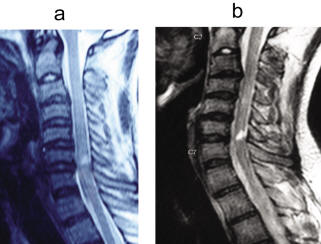

Thoracic Spinal Cord Injury without Radiographic Abnormality ...

Radiographic Abnormality Following Minor Trauma in Adult Young Dae Kim, M.D., Spinal cord injury without radiographic abnormality often occurs at cervical spine after major trauma predominantly in the skeletally immature pediatric population. ... Fetch Doc